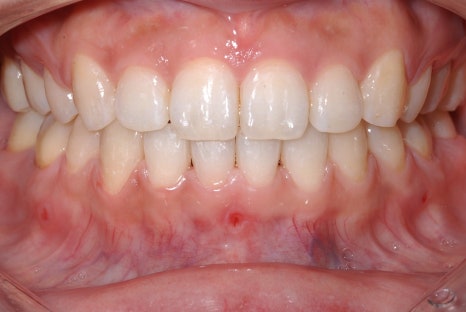

<교정치료 전후 사진>

치료기간: 23.05.15 - 24.10.21 (약 1년 6개월)

진행한 치료: 덧니, 치열 개선

치료기간: 23.01.18 - 24.6.04 (약 1년 6개월)

진행한 치료: 돌출, 중심선 개선

*치료 전후 사진은 환자의 동의하에 게재하였으며, 동일한 환경과 조건에서 촬영된 전후 사진입니다.